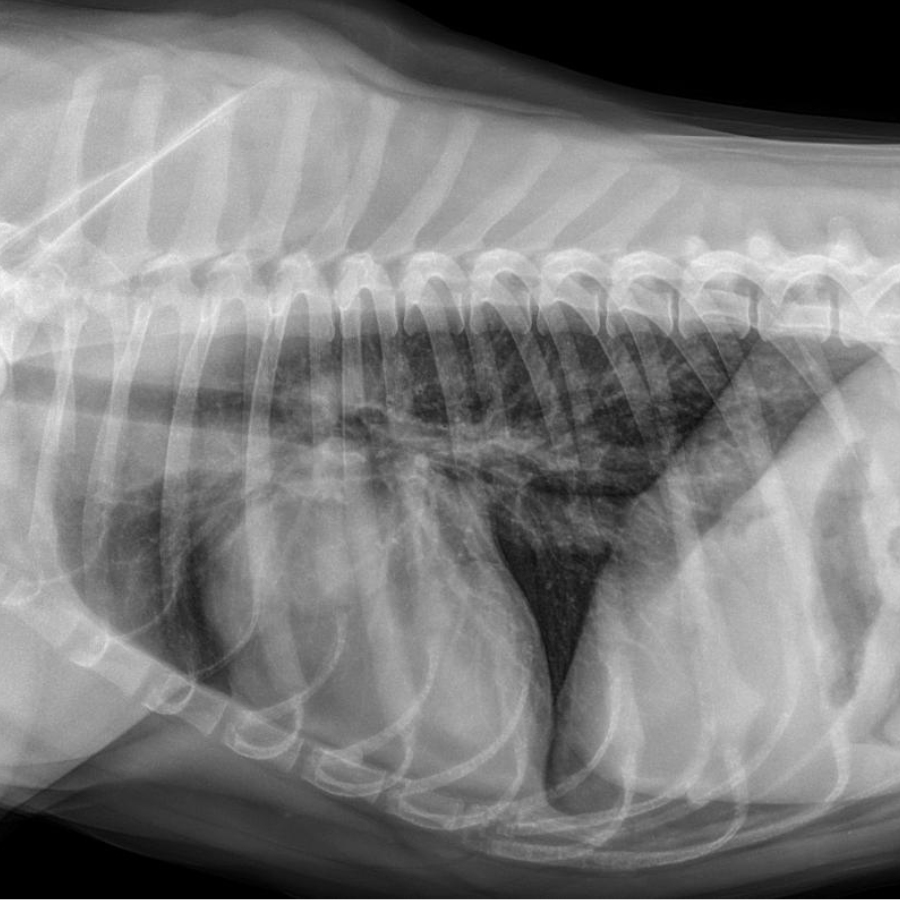

Radiology

We have a state of the art digital radiology equipment that makes viewing x-rays for us simple and quick. Radiology can be used as a diagnostic tool for fractures, hip dysplasia, heart disease, detecting masses, obstructions, and more. Anything that our doctors need further analysis on can be sent to a radiologist.